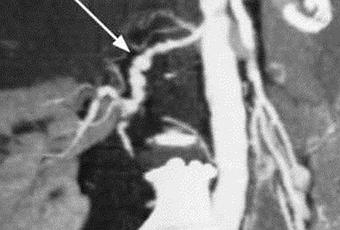

L'échographie Doppler des vaisseaux (image 35, voir l'onglet en couleur), le CT scan avec opacification (image 12.1) et l'IRM permettent de juger des dimensions du rein, de l'épaisseur de sa parenchyme, de l'état du système pyélo-caliciel et des vaisseaux rénaux.

L'urographie excrétrice donne une idée sur l'anatomie et les capacités fonctionnelles des reins et il est raisonnable de la faire pendant l'aortographie. La dernière permet de différencier les formes vasorénale et parenchymateuse de l'hypertension néphrogène et d'effectuer un traitement endovasculaire de la sténose de l'artère rénale. La sténose de l'artère rénale se manifeste sous forme d'un rétrécissement net de sa lumière avec une dilatation présténotique et postobstructionniste (image 12.2, а).

La dysplasie fibromusculaire atteint les tiers moyen et distal de l'artère et se caractérise par une structure moniliforme (sous forme de fil de perles) (voir image 12.1). Le critère angiographique de la thrombose ou de l'embolie de l'artère rénale - c'est son amputation au niveau du tronc vasculaire principal. L'anévrisme de l'artère rénale se manifeste sous forme de protrusion sacciforme ou fusiforme de la paroi vasculaire.

а - la sténose de l'artère rénale (flèche); b- la dilatation de la partie rétrécie par ballonnet (flèche); c- la sténose est supprimée à l'aide de remplacement de l'artère par une endoprothèse (flèche)